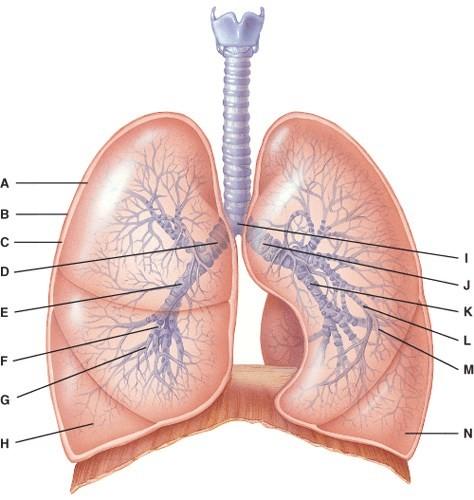

Where is the structure that regulates air flow to the alveolus?

- G

- M

- H

- A

- None of the above

B

What is line J pointing to?

- Right secondary bronchus

- Left secondary bronchus

- Right primary bronchus

- Left primary bronchus

- Carina

D

Where is the right bronchiole?

- F

- G

- H

- L

- M

B

What lines are pointing to tertiary bronchi?

- E and K

- D and J

- F and L

- H and M

- A and B

C

What is line B pointing to?

- Carina

- Visceral pleura

- Parietal pleura

- Pleural cavity

- Diaphragm

C

In this portion of the lungs, the epithelial lining is simple squamous.

- A

- B

- C

- D

- E

E

This is the primary gas exchange structure.

- A

- B

- C

- D

- E

E

What is line C pointing to?

- Terminal bronchiole

- Respiratory bronchiole

- Alveolar ducts

- Alveolar sac

- Alveoli

C

Where is the terminal bronchiole?

- A

- B

- C

- D

- E

A

This provides disease resistance within the lungs.

- A

- B

- C

- D

- None of the above

D

Which cells are the main sites of gas exchange?

- A

- B

- C

- D

- All of the above

C

Which cell secretes surfactant?

- A

- B

- C

- D

- None of the above

A